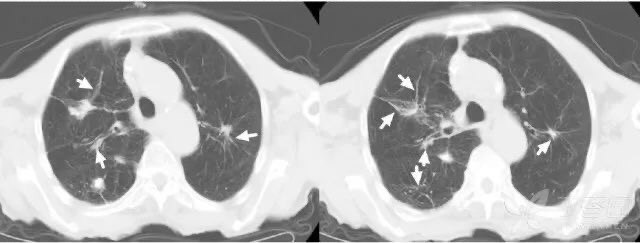

1.3 肺水肿:

患者脑出血入院,治疗后呼吸深大急促,并出现上肢与脸部水肿。

急查胸部 CT,见双肺自肺门向外弥漫基本对称的片絮状影(蓝箭),双侧胸腔后部可见液体(白箭)。